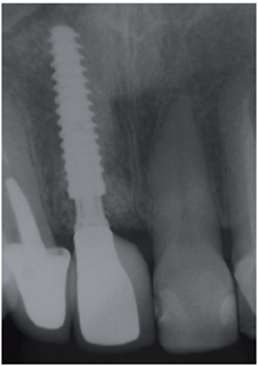

Paciente A.N., sexo feminino, 54 anos, procurou a clínica odontológica com fistula na região do elemento 11 (Figura 1). Foi solicitada tomografia computadorizada Cone Beam da região (Figura 2). Ao exame tomográfico foi diagnosticada a lesão periapical extensa, com perda óssea, envolvendo o elemento 11 (Figura 3). O plano de tratamento proposto foi a exodontia do elemento 11, curetagem da lesão e instalação imediata de um implante Cone Morse, juntamente com o procedimento de ROG, fazendo uso de biomaterial de origem bovina (Bio-Oss 0,25) e membrana de PTFE-d (Cytoplast TXT–200, Osteogenics – Lubbock TX, EUA) no mesmo momento cirúrgico.

Após a conclusão desses passos pelo laboratório, a prótese do elemento 12 foi cimentada com fosfato de zinco e a prótese sobre o pilar Ideale foi parafusada e torqueada a 10 Ncm (Figura 36). O orifício de acesso foi restaurado com resina fotopolimerizável (Figura 37). Uma radiografia final foi realizada, demonstrando o perfeito assentamento da coroa sobre o pilar Ideale.